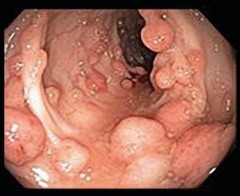

(C) Familial adenomatous polyposis

(precursor to colon cancer)